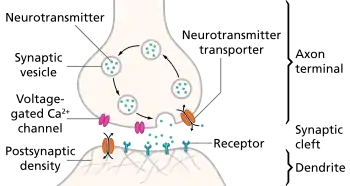

Monoamines

Monoamines are neurotransmitters that include serotonin, dopamine, norepinephrine, and epinephrine.[32]

Monoamine hypothesis of depression

Many antidepressant drugs acutely increase synaptic levels of the monoamine neurotransmitter, serotonin, but they may also enhance the levels of norepinephrine and dopamine. The observation of this efficacy led to the monoamine hypothesis of depression, which postulates that the deficit of certain neurotransmitters is responsible for depression, and even that certain neurotransmitters are linked to specific symptoms. Normal serotonin levels have been linked to mood and behaviour regulation, sleep, and digestion; norepinephrine to the fight-or-flight response; and dopamine to movement, pleasure, and motivation. Some have also proposed the relationship between monoamines and phenotypes such as serotonin in sleep and suicide, norepinephrine in dysphoria, fatigue, apathy, cognitive dysfunction, and dopamine in loss of motivation and psychomotor symptoms.[33] The main limitation for the monoamine hypothesis of depression is the therapeutic lag between initiation of antidepressant treatment and perceived improvement of symptoms. One explanation for this therapeutic lag is that the initial increase in synaptic serotonin is only temporary, as firing of serotonergic neurons in the dorsal raphe adapt via the activity of 5-HT1A autoreceptors. The therapeutic effect of antidepressants is thought to arise from autoreceptor desensitization over a period of time, eventually elevating firing of serotonergic neurons.[34]

Serotonin

The serotonin "chemical imbalance" theory of depression, proposed in the 1960s, [35] is not supported by the available scientific evidence.[35][36] SSRIs alter the balance of serotonin inside and outside of neurons: their clinical antidepressant effect (which is robust in severe depression[37]) is likely due to more complex changes in neuronal functioning which occur as a downstream consequence of this.[38]

Initial studies of serotonin in depression examined peripheral measures such as the serotonin metabolite 5-Hydroxyindoleacetic acid (5-HIAA) and platelet binding. The results were generally inconsistent, and may not generalize to the central nervous system. However evidence from receptor binding studies and pharmacological challenges provide some evidence for dysfunction of serotonin neurotransmission in depression.[39] Serotonin may indirectly influence mood by altering emotional processing biases that are seen at both the cognitive/behavioral and neural level.[40][39] Pharmacologically reducing serotonin synthesis, and pharmacologically enhancing synaptic serotonin can produce and attenuate negative affective biases, respectively. These emotional processing biases may explain the therapeutic gap.[40]